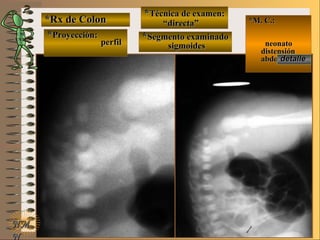

*Rx de Estómago*Rx de Estómago

**Proyección:Proyección:

**Técnica de examen:Técnica de examen:

**Segmento examinado:Segmento examinado:

*M. C.:neonato*M. C.:neonato

con vómitocon vómito

NMNM

frentefrente

““directa de abdomen”directa de abdomen”

panorámicapanorámica

A-A-El examen es normal o patológico?El examen es normal o patológico?

Examen patológico de estómago sinExamen patológico de estómago sin

contraste (directa) en proyección decontraste (directa) en proyección de

B-B-La patología es congénita o adquirida?La patología es congénita o adquirida?

Patología congénita en neonato; verPatología congénita en neonato; ver

Clasificación General UNTClasificación General UNT

C-C-Puede describir la o las imágenes patológicas?Puede describir la o las imágenes patológicas?

Se identifica una “burbuja” única que se ex-Se identifica una “burbuja” única que se ex-

tiende oblicuamente desde hipocondrio izquier-tiende oblicuamente desde hipocondrio izquier-

do hasta flanco derecho y ocupa la región um-do hasta flanco derecho y ocupa la región um-

bilical determinado por una atresia de píloro;bilical determinado por una atresia de píloro;

nótese la sonda naso-gástricanótese la sonda naso-gástrica